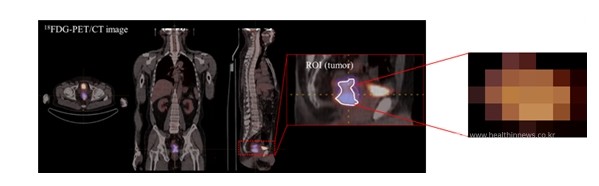

연구팀은 의료분야에서 다양하게 활용되고 있는 인공지능에 착안하여 국소 진행성 직장암 환자 156명을 대상으로 양전자방출단층촬영(이하 PET) 영상 데이터 기반의 기계학습 모델을 이용해 수술 전 항암방사선치료 결과 완전관해 예측 정확도를 비교 분석했다.

분석 결과, 원자력병원 환자의 항암방사선치료 전 종양 PET 영상 데이터 및 치료 후 결과를 학습시킨 기계학습 모델의 완전관해 예측 정확도는 76%로 평가되었다.

이 과정에서 연구팀은 원자력병원 및 부천순천향병원 양기관에서 다양한 PET 영상 데이터 및 치료 후 결과자료를 확보하고, 측정기관 간의 장비 및 이미지 추출·분석법 등의 차이에 따른 PET 영상의 변동성을 개선하여 분석 결과의 정확도를 높였다.